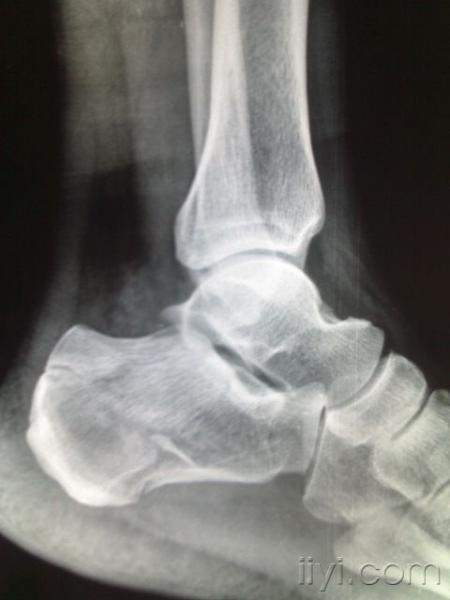

儿童脚疼的常见原因却被经常漏诊的问题北京和平里中西医结合医院骨科

儿童踝关节正常x片

正常儿童脚踝骨图片

7岁儿童脚x光片